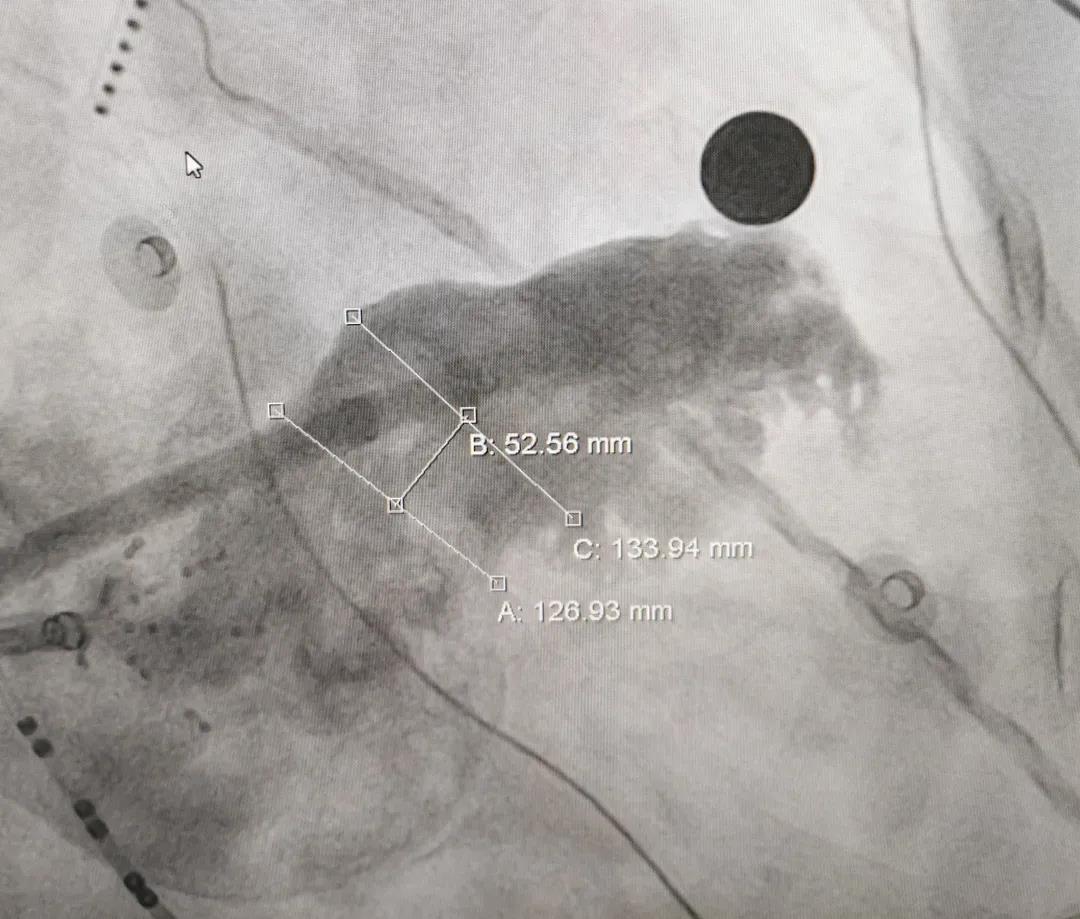

患者男,63岁,间断心悸病史11年。术前TEE显示左心耳无血栓,拟行房颤射频消融结合左心耳封堵术。左心耳丈量锚定区约为27mm,封堵区约为25mm,选用LAmbre?2632封堵器进行封堵,达到了梦想的封堵成效。LAmbre?怪异的锚定机造能确保左心耳封堵器不变牢固,牵拉测试极度不变,切合COST准则,随后开释封堵器。